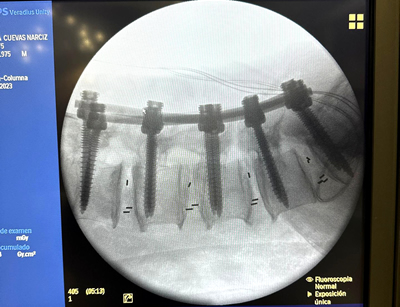

IMÁGENES

Galería de imágenes